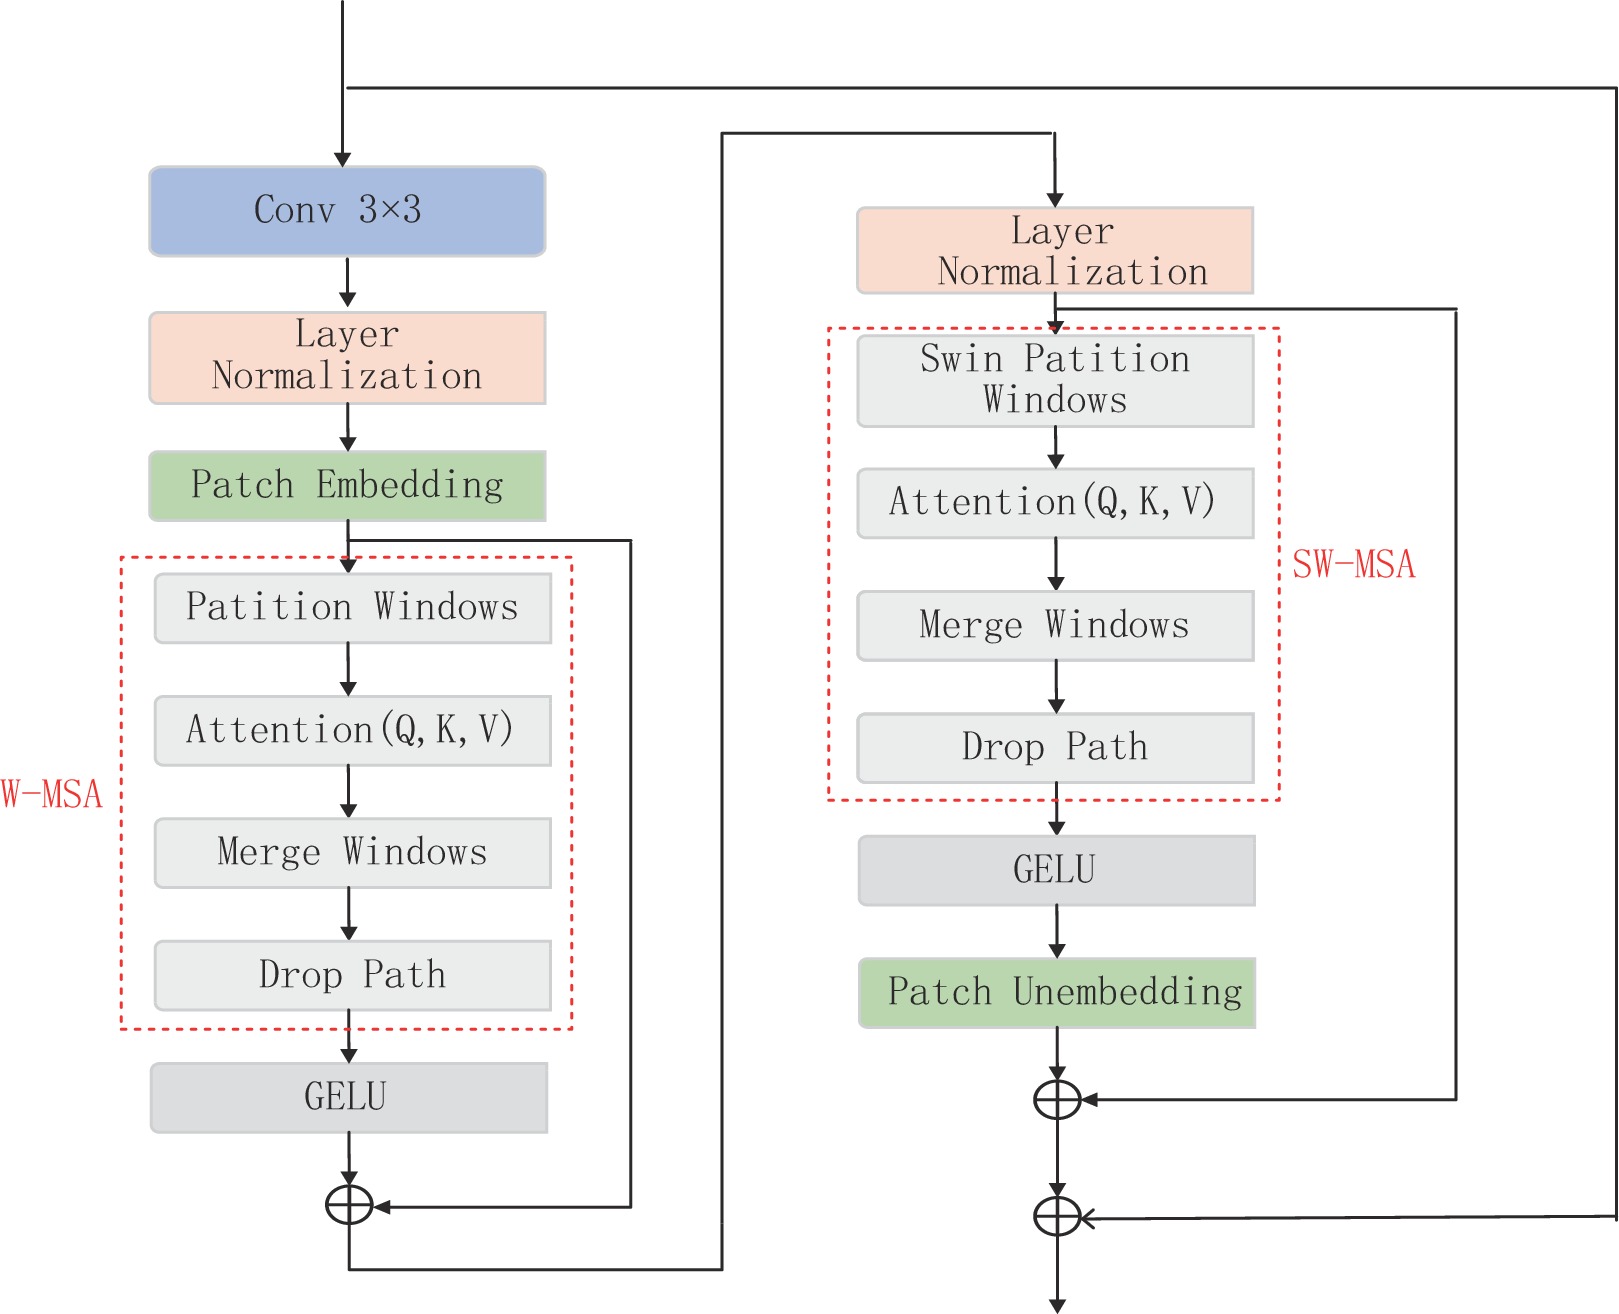

本文中提出的CNN和Transformer耦合模块(CTCB)由3部分组成,第1部分是3×3的卷积层(conv);第2部分是归一化层(layer normalization),多头自注意力(W-MSA)和GRLU激活函数;第3部分是归一化层(layer normalization),具有滑动窗口的多头自注意力(SW-MSA)和GELU激活函数,且采用了多残差机制。

CNN和Transformer耦合模块(图1),实现了CNN和Transformer优势的融合。这样设计的网络,一方面具有CNN的局部感知和参数共享特性,将原始图像作为输入,直接从大量样本中学习相应特征,避免使用复杂的特征提取过程捕获局部结构;另一方面又具有Transformer的动态注意全局特征和更好的泛化能力,且运用了滑动窗口机制,能在参数较少的情况下提取有效信息实现去噪。

$ {\boldsymbol{P}}_{Q} $ ,$ {\boldsymbol{P}}_{K} $ ,$ {\boldsymbol{P}}_{V}, $ 是跨不同窗口共享的投影矩阵,且$ \boldsymbol{Q} $ ,$ \boldsymbol{K} $ ,$ \boldsymbol{V}\in {R}^{{M}^{2}\times d} $ ,其中d为Q/K的维度,则注意力矩阵在对应窗口中自注意力机制计算为:$$ {\boldsymbol{A}}({\boldsymbol{Q}},{\boldsymbol{K}},{\boldsymbol{V}}) = {\rm{soft}}\;\max \left( {\frac{{\boldsymbol{ Q}}{{\boldsymbol{K}}^{\rm{T}}}}{{\sqrt {{d}} }} + {\boldsymbol{B}}} \right){\boldsymbol{V}} \text{,} $$ (2) 其中B是可学习的相对位置编码。本文实现两次自注意力计算,并将结果串联起来构成多头自注意力(W-MSA),之后连接GELU非线性激活层完成第2部分。第3部分通过移动窗口,再次进行多头自主注意力机制(SW-MSA),并连接GELU非线性激活层。